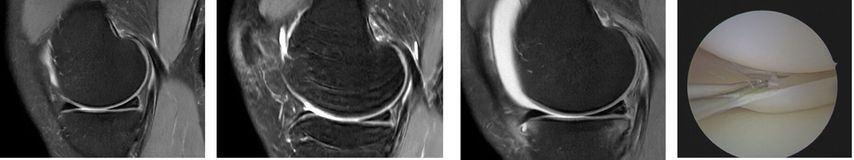

Behrendt stellte im Zuge seines Vortrags den Fall einer 25 Jahre alten Handballspielerin mit Distorsionstrauma im Mai 2023 vor. Bei einer MR-gestützten Partialruptur des vorderen Kreuzbandes mit geringer subjektiver Instabilität wurde zunächst konservativ behandelt. Im Verlauf zeigten sich jedoch zunehmende Hyperintensität am Innenmeniskus-Hinterhorn und eine Restinstabilität beim Handballspielen. Ein Jahr nach dem Unfall führte die zunehmende Symptomatik zu einem klaren Meniskusriss, sodass eine Kreuzbandersatzplastik und eine Rekonstruktion des Innenmeniskusrisses durchgeführt wurden (Abb.1). Diese Fallvignette verdeutlicht, dass nach unzureichender Versorgung eines vorderen Kreuzbandrisses das Risiko für zusätzliche Meniskus- und Knorpelschäden hoch ist. Eine Metaanalyse zeigte, dass dies in 88 % der Studien (35 von 44) auftrat. Kritische Zeitgrenzen lagen bei sechs Monaten für Meniskus- und zwölf Monaten für Knorpelschäden; danach stieg die Wahrscheinlichkeit weiterer Schädigungen deutlich an. Mit zunehmendem zeitlichem Abstand zum Kreuzbandriss verschlechtert sich zudem die Rekonstruierbarkeit der Menisken.8